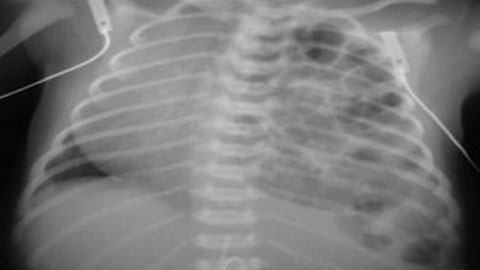

Kết quả chụp phim ổ bụng của bé T